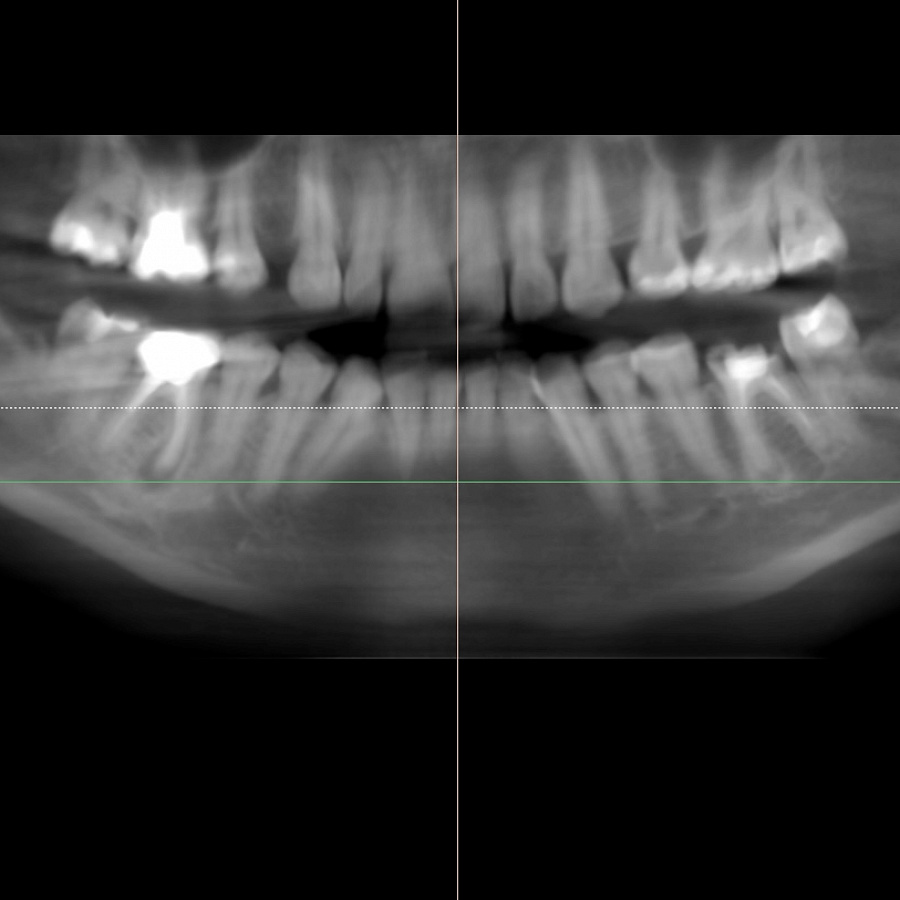

В ходе диагностики мы выяснили, что нижние шестерки вылечить невозможно. В таком случае необходимо удалить зубы и установить имплантаты.

Пациентка начала ортодонтическое лечение и за 5 месяцев до окончания лечения ей удалили нижние шестерки и поставили импланты. За месяц до конца лечения установили формирователи десны. На момент снятия брекетов были сняты слепки под постоянные коронки на имплантатах.